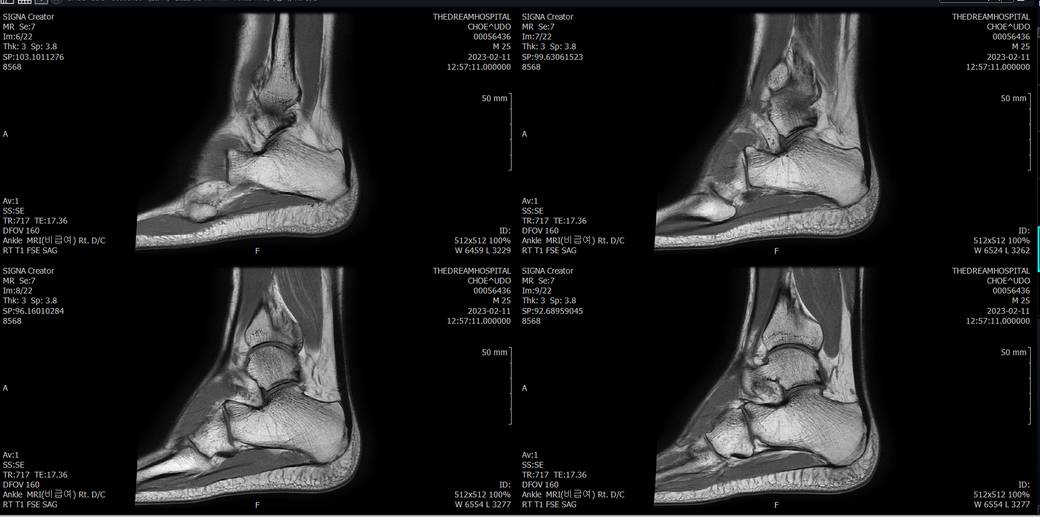

오른발목 mri 전체사진입니다. 제가 병원을 갈수없는상황인지라.... 봐주시면 감사하겠습니다.

엑스레이에서는 문제가 없다고 하여 오른발목 mri촬영했습니다.

우선 전반적으로 봤을 때 큰 이상은 없어보입니다.

전거비인대 등도 저명한 손상은 없는 것 같아 보이지만, 어느 부분의 통증 등으로 인해 촬영을 하셨는지 말씀을 해주신다면 보다 정확한 병변파악이 가능하겠으며, 병원에서 판독이 완료되신다면 전화 등으로 문의를 해보시는 것이 좋겠습니다.